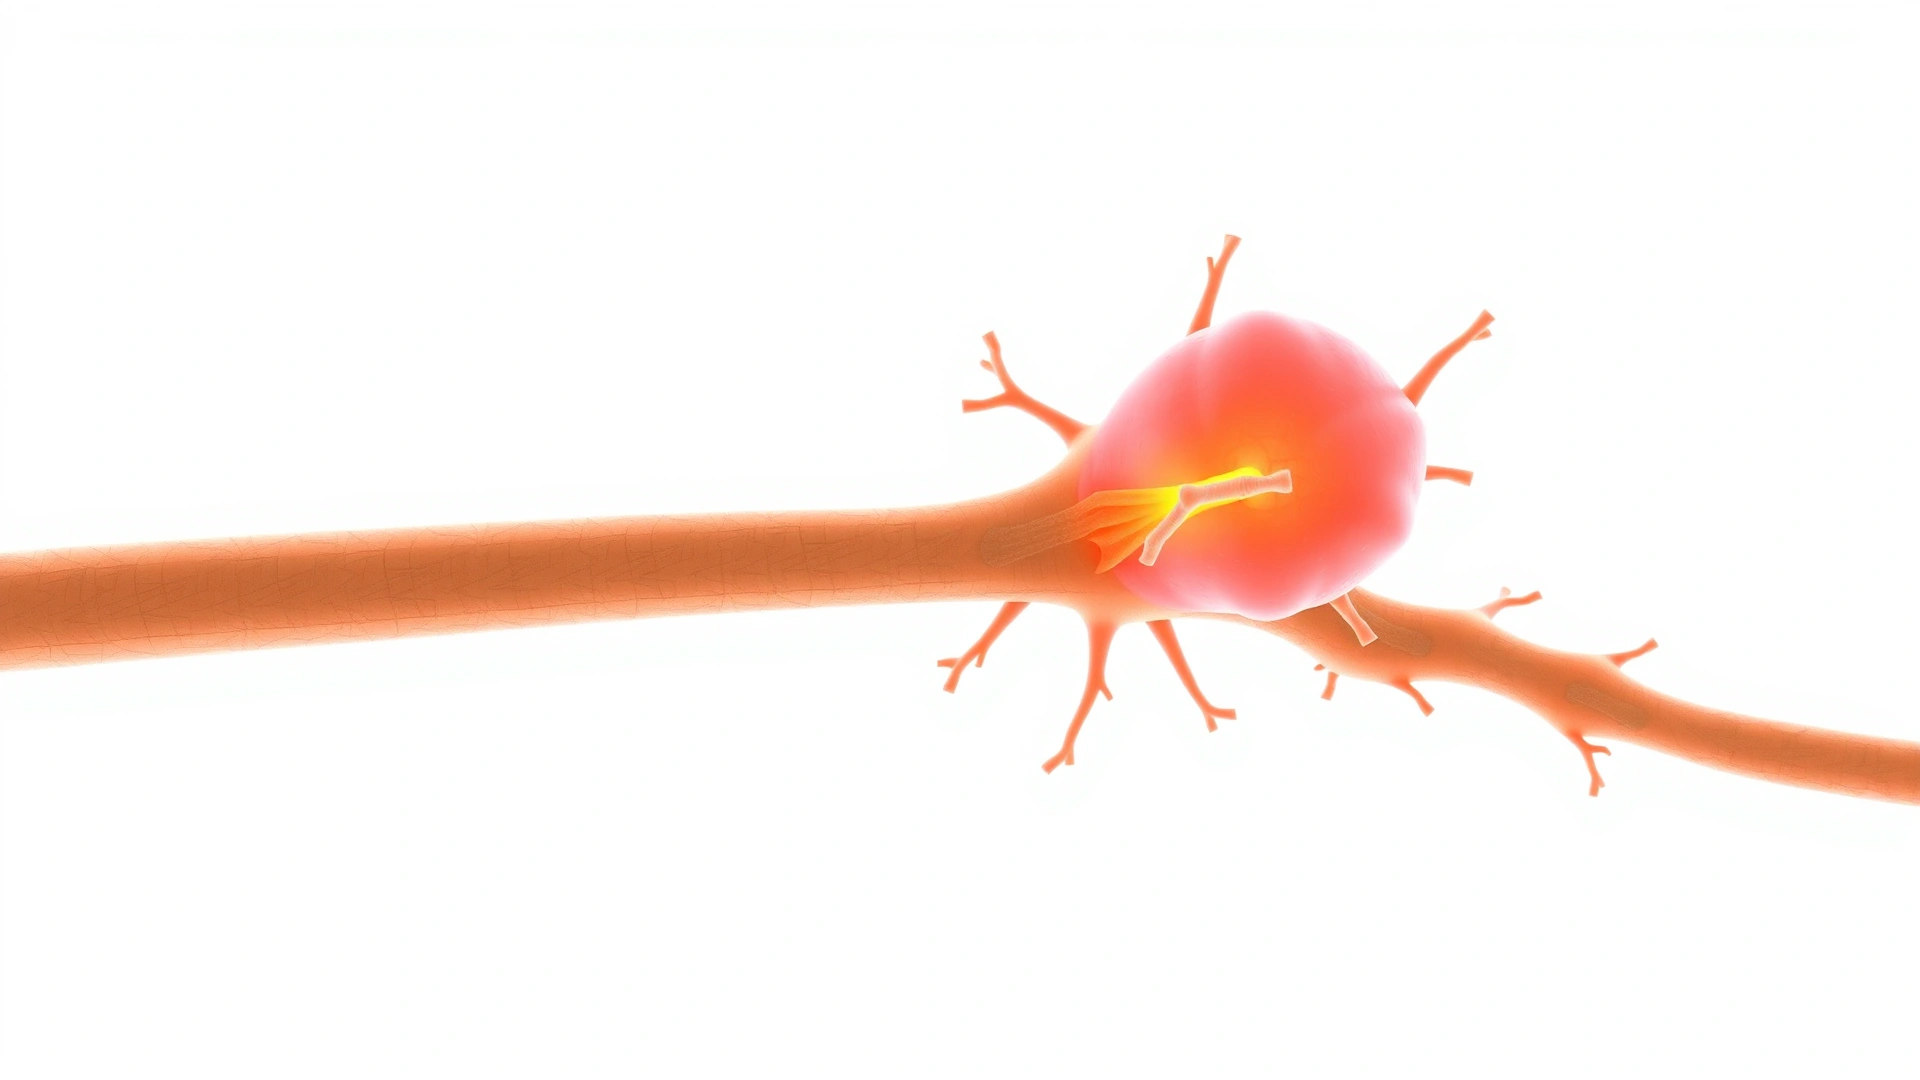

سواء كنت مُربِّياً جديداً أو خبيراً في تربية القطط، فإن ملاحظة أي كتلة أو تورُّم على جسم قطك كفيلة بإثارة القلق. أحد الأسباب المحتملة لهذه الكتل هو الورم الشفاني (Schwannoma)، وهو ورم حميد ينشأ من الخلايا الشفانية التي تُغلِّف الأعصاب الطرفية. مع أن هذا الورم نادر الحدوث عند القطط، فإن التعرّف المبكر عليه يُعدُّ مفتاحاً للعلاج الناجح وتجنُّب المضاعفات.

الورم الشفاني هو نموٌّ غير طبيعي في الخلايا الشفانية المسؤولة عن تكوين غمد الميالين الذي يحيط بالأعصاب الطرفية ويحميها. على الرغم من كونه ورماً حميداً في العادة، فإنه قد يسبب ضغطاً على الأعصاب أو الأنسجة المجاورة، ما يؤدي إلى أعراض عصبية أو ألم موضعي حسب موقعه.